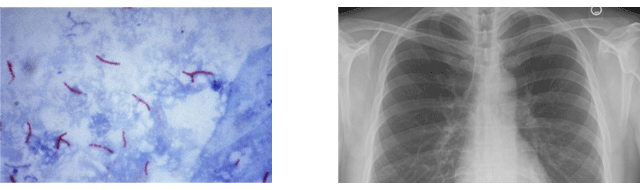

È£Èí±â Áúȯ

¿ì¸®³ª¶ó´Â ¾ÆÁ÷µµ Æó°áÇÙÀÇ À¯º´À²°ú »ç¸Á·üÀÌ ³ô°í, Èí¿¬ ¹× °¢Á¾ ȯ°æÀÎÀÚÀÇ ¿µÇâÀ¸·Î Æó¾ÏÀÌ ±Þ°ÝÈ÷ Áõ°¡Çϰí ÀÖ½À´Ï´Ù. ´õºÒ¾î Èí¿¬, Àα¸°í·ÉÈ, ´ë±â¿À¿°, ÀÛ¾÷Àå³» ºÐÁø µîÀº ¸¸¼ºÆó¼â¼º ÆóÁúȯ, õ½Ä, ¾Ë·¯Áö¼º ºñ¿°ÀÇ Áõ°¡¸¦ À¯¹ßÇϰí ÀÖÀ¸¸ç Áö¿ª»çȸ Æó·Å, »ç½º, ½ÅÁ¾µ¶°¨, ¸Þ¸£½º µîÀº È£Èí±â ÁúȯÀÇ Á߿伺À» Àß ´ëº¯Çϰí ÀÖ½À´Ï´Ù.